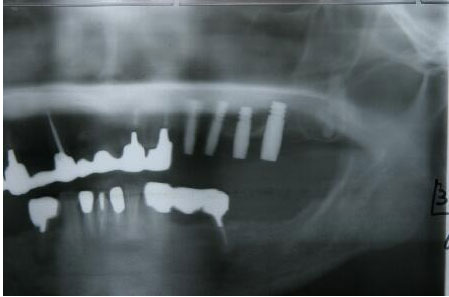

術前エックス線写真

上顎洞の下縁の骨が1〜3ミリ程度しかなくソケットリフトでは不可能なのでサイナスリフトの選 択となる